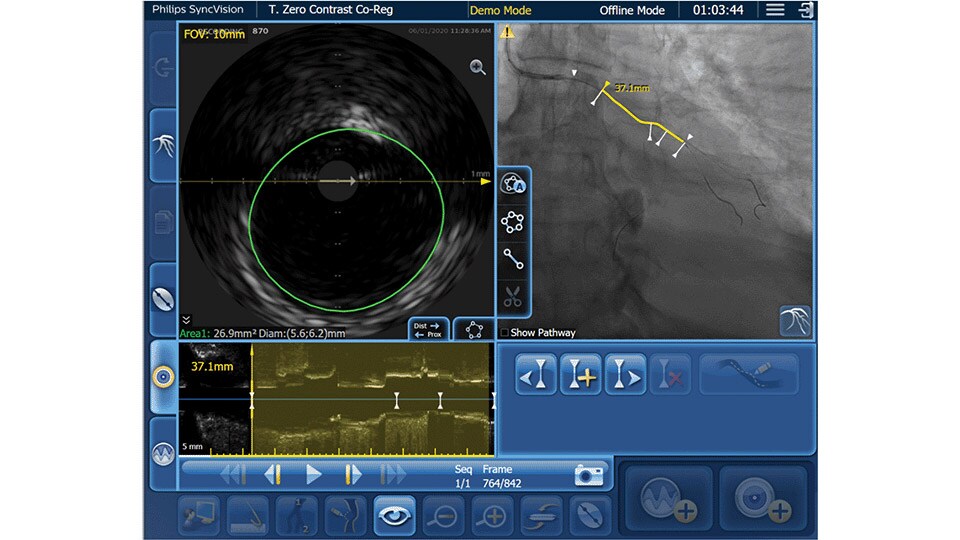

Only Philips instant-wave free radio (iFR) has co-registration for advanced physiologic guidance, allowing you to precisely determine lesion location and severity.

As an alternative or adjunct to IVUS Co-registration, iFR pullback can be co-registered onto the angiogram to assess both the degree and length of vessel stenosis.

New invasive imaging techniques and co-registration software allows PCI to be performed with limited amounts of contrast, even with zero-contrast use, to reduce the risk of CI-AKI for all patients, and especially those with renal insufficiency.

Philips PCI guidance solutions incorporate non-invasive and adjunctive IVUS and iFR modalities, requiring less contrast for proper diagnosis.